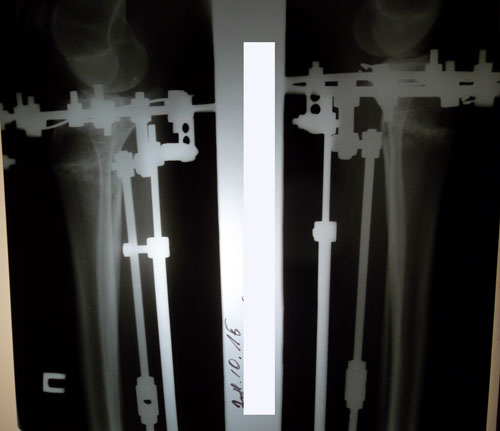

РЕНТГЕН В 20  ДНЕЙ ПОСЛЕ ОПЕРАЦИИ